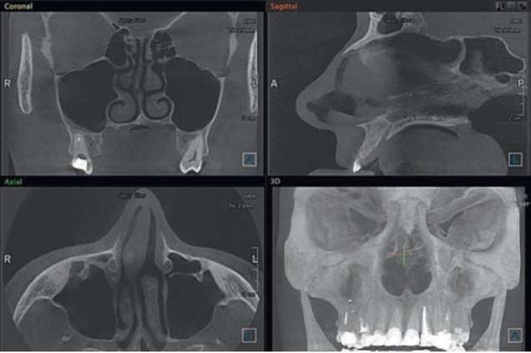

Дифференциальная диагностика

Следует проводить дифференциальную диагностику с массивными апикальными очагами, которые могут достигать действительно больших размеров, ремоделируя дно ВС, практические достигая орбитальной стенки ВС и вместе с этим не нарушая адекватную работу мукоцилиарного клиренса и дренажа ВС (рис. 5.88); а также с острым и хроническим остеомиелитом верхней челюсти, заболеваниями тройничного нерва, риногенным синуситом (рис. 5.89), опухолями (рис. 5.90), в том числе злокачественными новообразованиями, аллергическими воспалениями пазухи (см. рис. 5.89).

image

Рис. 5.88. Резидуальная киста верхней челюсти справа, ремоделирующая дно верхнечелюстного синуса

Для проведения дифференциальной диагностики с радикулярной кистой (одонтогенным апикальным очагом) и мукоцеле (ретенционной кисты), исходящей из мембраны Шнайдера, достаточно провести КЛКТ-исследование и акцентировать свое внимание на наличии или отсутствии кортикального венчика над верхним отделом кисты, в случае если он будет обнаружен, то при наличии одонтогенной причины (нелеченого или некачественно леченного зуба) можно утверждать, что данное образование имеет одонтогенную природу. Перфоративный синусит следует дифференцировать от радикулярной кисты, ремоделирующей дно ВС. Отличительный признак кисты - отсутствие попадания жидкости из полости рта в нос и воздуха из него в рот (см. рис. 5.88).